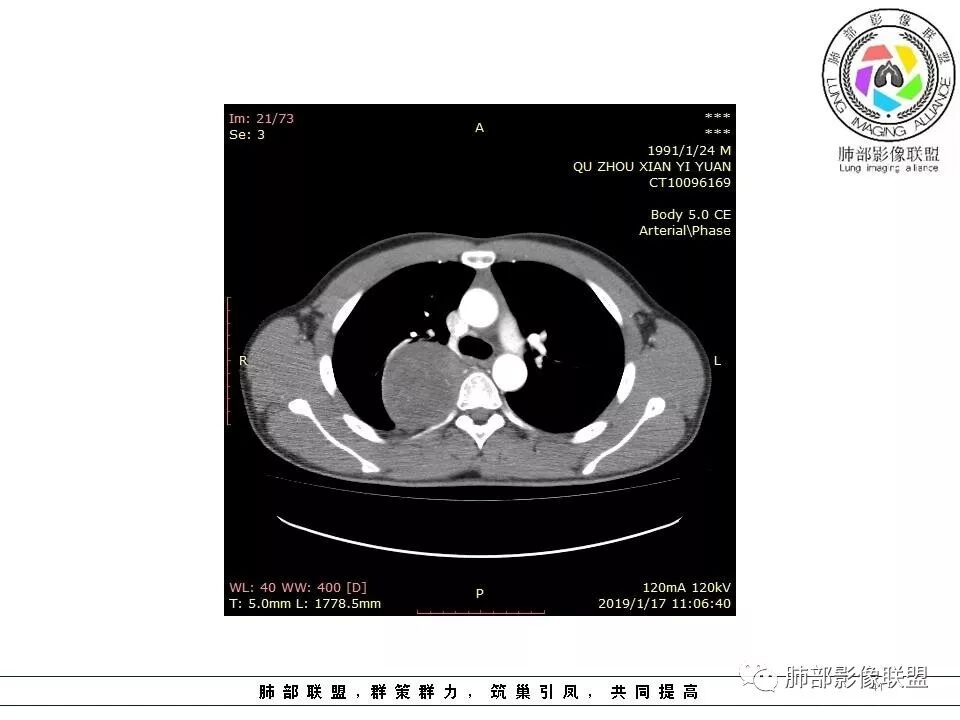

右后纵膈脊柱旁软组织占位,形态规则类圆,边缘光整,肺组织受压,胸膜尾,肋间动脉供血。中度不均匀延迟强化。

右后纵膈脊柱旁软组织占位,边界清晰,光整,肺组织受压。胸膜被掀起,肋间动脉供血,中度不均匀延迟强化。考虑神经鞘瘤,不除外纤维瘤

右后纵膈脊柱旁软组织影,与纵隔结构分界不清,形态规则类圆,边缘光整,肺组织受压,胸膜尾,肋间动脉供血。肺动脉推移,中度不均匀延迟强化。考虑神经来源,神经鞘瘤,神经纤维瘤二者不易鉴别。

青年男性,间断胸痛;右侧脊柱旁可见一类圆形软组织密度影,密度欠均匀,增强扫描呈轻中度持续强化,邻近肺组织及肺动脉推移,可见肋间动脉供血,部分胸膜下脂肪可见,部分层面似见与右侧椎间孔相连。考虑后纵隔神经源性肿瘤。

青年男性,间断胸痛。右后纵膈脊柱旁软组织占位,形态规则类圆,边缘光整,肺组织受压,D字征,胸膜尾,肋间动脉供血。中度不均匀延迟强化。无支气管进入考虑来源于肺外、肿块与脊柱间未见明显脂肪间隙,考虑来源于胸膜外,考虑神经源性肿瘤,建议穿刺活检。

1.右上胸内脊柱旁类圆形肿块,质地似乎比较坚实,密度稍显不均,但未显示明确的坏死。

如此密度形态的病灶位于肺边缘首先应当想到孤立性纤维瘤,可相邻胸膜未见明显的异常强化和胸膜方向延伸。

2.肋间动脉病供血也提示肿块来自后纵隔?

4.静脉期轻度不均匀强化,注意不是环形强化,亦未见明确的“AB区”,这点也不支持神经鞘瘤。临床及病灶轻度强化都不支持副节瘤。